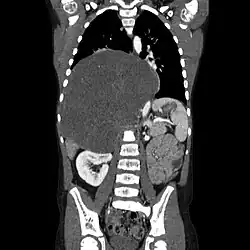

Ganglioneurom je vzácný typ benigního tumoru autonomní nervů pocházejících z nediferencovaných buněk neruální lišty sympatika.[1] Samotný ganlioneurom je složen z buněk zcela diferencovaných.[2]

Ganglioneuroma se nejčastěji vyskytuje v oblasti břicha, nicméně tento typ nádoru můžeme najít kdekoliv, pokud je zde i vhodná nervová tkáň. Ganglioneuromy jsou typicky bez příznaků, avšak tumor v oblasti hrudníku může způsobovat například dýchací potíže nebo bolest na hrudníku. Naopak nádor v oblasti míchy způsobuje bolesti zad nebo výraznou ztrátu svalové hmoty.